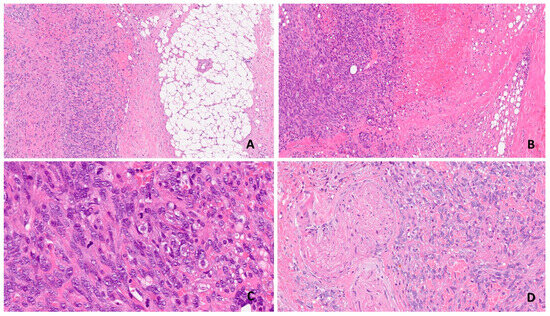

Primary Epithelioid Angiosarcoma of the Breast Masquerading as Carcinoma

by S. Muzumder, P. Das, M. Kumar, S. Bhasker, C. Sarkar, K. Medhi, V. K. Iyer and G. K. Rath

Curr. Oncol. 2010, 17(1), 64-69; https://doi.org/10.3747/co.v17i1.451 - 1 Feb 2010

Cited by 25 | Viewed by 1133

Abstract

Here we report a case of primary epithelioid angiosarcoma (EAS) of the breast occurring in a 30-year-old woman. Following fine-needle asspiration cytology (FNAC) and tru-cut biopsy, the patient was initially diagnosed with mammary carcinoma and thereafter underwent modified radical [...] Read more.

Here we report a case of primary epithelioid angiosarcoma (EAS) of the breast occurring in a 30-year-old woman. Following fine-needle asspiration cytology (FNAC) and tru-cut biopsy, the patient was initially diagnosed with mammary carcinoma and thereafter underwent modified radical mastectomy. Postoperative histopathologic examination and immunohistochemistry revealed a diagnosis of primary epithelioid angiosarcoma of the breast. The patient received postoperative radiotherapy to the chest wall and was started on adjuvant thalidomide. Preoperatively, EAS can be mistaken for carcinoma because it is difficult to appreciate the typical morphology on FNAC or tru-cut biopsy. Indeed, this is an area of potential diagnostic error because, nowadays, neoadjuvant therapy is often instituted after core biopsy of a breast mass. This case is being reported not only for its diagnostic difficulty, but also because of its rarity in English literature. Full article